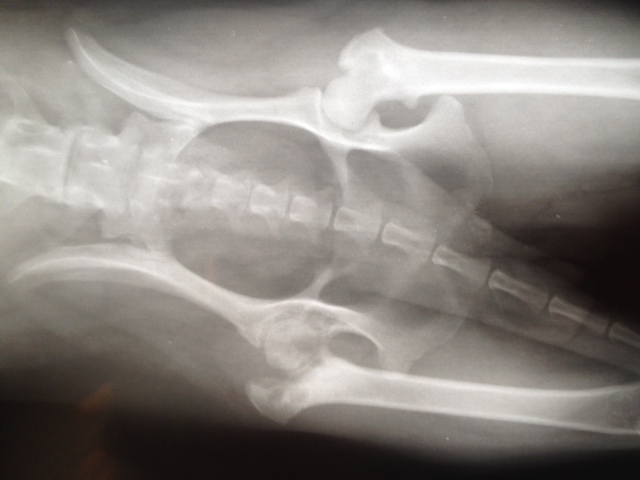

Felipas Vorderpfötchen ist nach der ersten Operation gut verheilt. Nun sollte eigentlich das 2. Vorderbeinchen drankommen und ebenso gerichtet werden.

Aber Felipa ließ das eine Hinterbeinchen neuerdings so eigenartig hängen und trat nicht mehr damit auf. Also ließen wir es abklären. Es stellte sich heraus, dass sich der Knorpel des Oberschenkelhalskopfes zersetzt.

Die Ursache dafür sind genetisch bedingte Durchblutungsstörungen. Das kommt bei einigen kleineren Rassen vor. Es hat nichts mit der OP am Vorderbein zu tun.

Aber da Felipa das Hinterbein nicht ordnungsgemäß benutzen kann, musste sie also nun erst dort operiert werden, damit sie hinten auftreten kann, wenn das andere Vorderbein operiert wird.

Unser tierischer Großtransport mit sechs Hunden, die alle Probleme mit Knochen hatten, ging in eine Spezialpraxis nach Berlin. Wir berichteten bereits.

Der Tierarzt Dr. Köhle hat nicht nur einen "Röntgenblick", sondern auch "Röntgenfinger" und natürlich einen Röntgenapparat.

Er und sein Team wie auch unsere Tierpflegerin Gabi mussten tüchtig zupacken, um für alle unsere Tierchen die optimale Lösung zu finden.